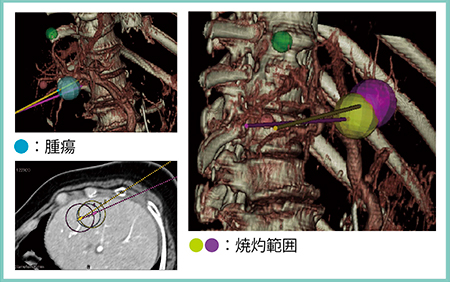

3D Sim-Navigator では,RVSにて同期表示された超音波画像とほぼ同一断面のCTやMRIのMPR画像上で腫瘍にマーキングを行うと,超音波画像上でも腫瘍がマーキングされる。そこに超音波ガイド下に電極針を穿刺し,針のマーキングを行う。この電極針を履歴登録して三次元ボリュームデータに反映させると穿刺ガイドラインが表示され,3D画像の中で腫瘍と電極針のオリエンテーションをつけることが可能となる。複数本穿刺では腫瘍と各電極針との位置関係が非常に明瞭となるため(図1),マルチポーラRFAやオーバーラップ法においては,きわめて有用なシミュレータとなる。

図1 シミュレータとしての3D Sim-Navigator